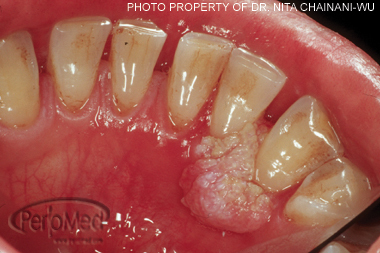

Verruciform Xanthoma

Hyperplastic condition - likely due to trauma

Lipid-laden histiocytes in the epithelium – XANTHOMA CELLS

Common on gingiva

Painless

Sessile (slightly elevated)

Papillary (roughened surface)

Mucosal, white, yellow, or red

<2cm

Multiple lesions possible